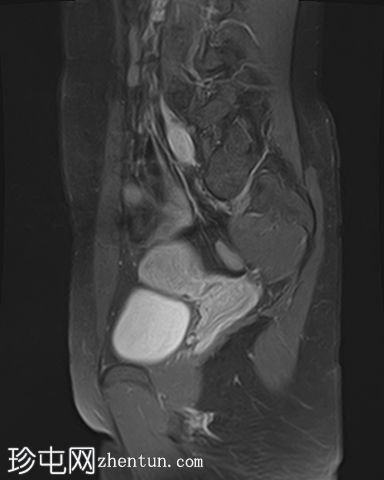

5.jpg

矢状位

T2

右侧卵巢出血性囊肿,T1成像呈中等信号,T2成像呈高信号,伴有薄内部分隔

左侧卵巢出血性囊肿,信号特征与右侧囊肿相似

左侧单纯性卵巢旁囊肿,T1成像呈低信号,T2成像呈高信号

此外,所有囊肿均未显示弥散受限或实性成分强化。

所有囊肿均仅显示薄层外周壁强化。

道格拉斯囊右侧可见轻度积液。

卵巢相关囊性病变边界相对清晰。信号特征可能因出血时间而异。

T2 加权成像通常显示高信号。 T2 阴影征提示存在慢性血液产物,更像子宫内膜异位症。

本例卵巢囊肿呈中等 T1 信号,类似于肌肉信号,T2 信号高,伴有薄内隔和外周壁强化。但无内部强化或弥散受限。STIR 序列显示与 T2 一致的信号,无任何脂肪成分。该表现提示卵巢出血性囊肿处于早期或消退期。

此外,左侧卵巢旁囊肿外观简单,T1 信号低,T2 信号高。